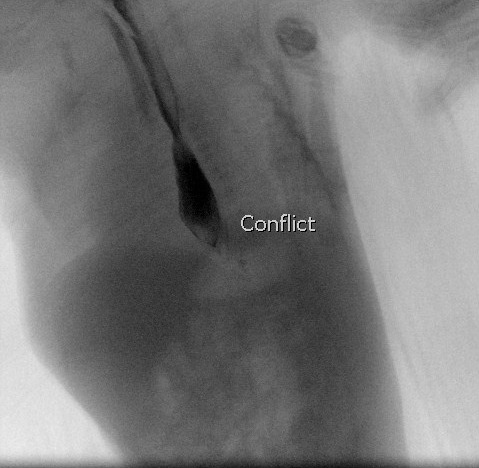

Se realiza un esofagograma, donde se observa paso de contenido al árbol bronquial, lo que sugiere una comunicación esofagotraqueal a través de una fístula en N. Trayecto descendente desde la tráquea hacia el esófago.

Esofagograma en el que se observa el paso de contraste a la vía respiratoria inmediatamente a la ingesta. Se observa el contraste en el bronquio principal derecho